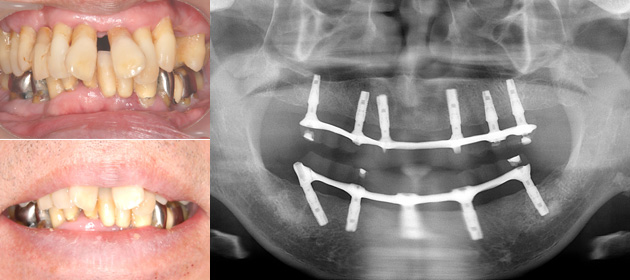

All-on-4 (6)の治療例

歯がグラグラして食べられない